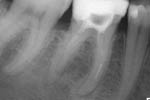

Revisionsbehandlung eines Unterkiefermolaren (37) vor geplanter Überkronung (Dr. Maik Göbbels) Download